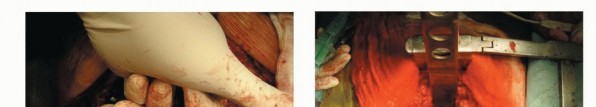

Positioning

The patient is placed prone over the Relton-Hall four-poster frame for the posterior approach to avoid compression to the vena cava.

A straight vertical midline incision is made over the spinous processes and is extended three vertebrae above and below the involved segment(s). The paraspinal muscles are dissected from the spinous processes and the laminae and then retracted laterally. If the patient underwent a posterior route biopsy, the tracts are carefully resected in a manner similar to that used in limbsalvaging procedures. After a careful dissection of the area around the facet joints, a large retractor, the articulated spinal retractor, which has a uniaxial joint in each limb and was designed for this surgery, is applied.

TECH FIG 1. A. Exposure. B. Ribs on the affected level are transected 3 to 4 cm lateral to the costotransverse joint.

By spreading the retractor and detaching the muscles around the facet joints, a wider exposure is then obtained. The operative field must be wide enough on both sides to allow dissection under the surface of the transverse processes. In the thoracic spine, the ribs on the affected level are transected 3 to 4 cm lateral to the costotransverse joint, and the pleura is bluntly separated from the vertebra(TECH FIG 1). To expose the superior articular process of the uppermost vertebra, the spinous and inferior articular processes of the neighboring vertebra are osteotomized and removed with dissection of the attached soft tissues, including the ligamentum flavum.